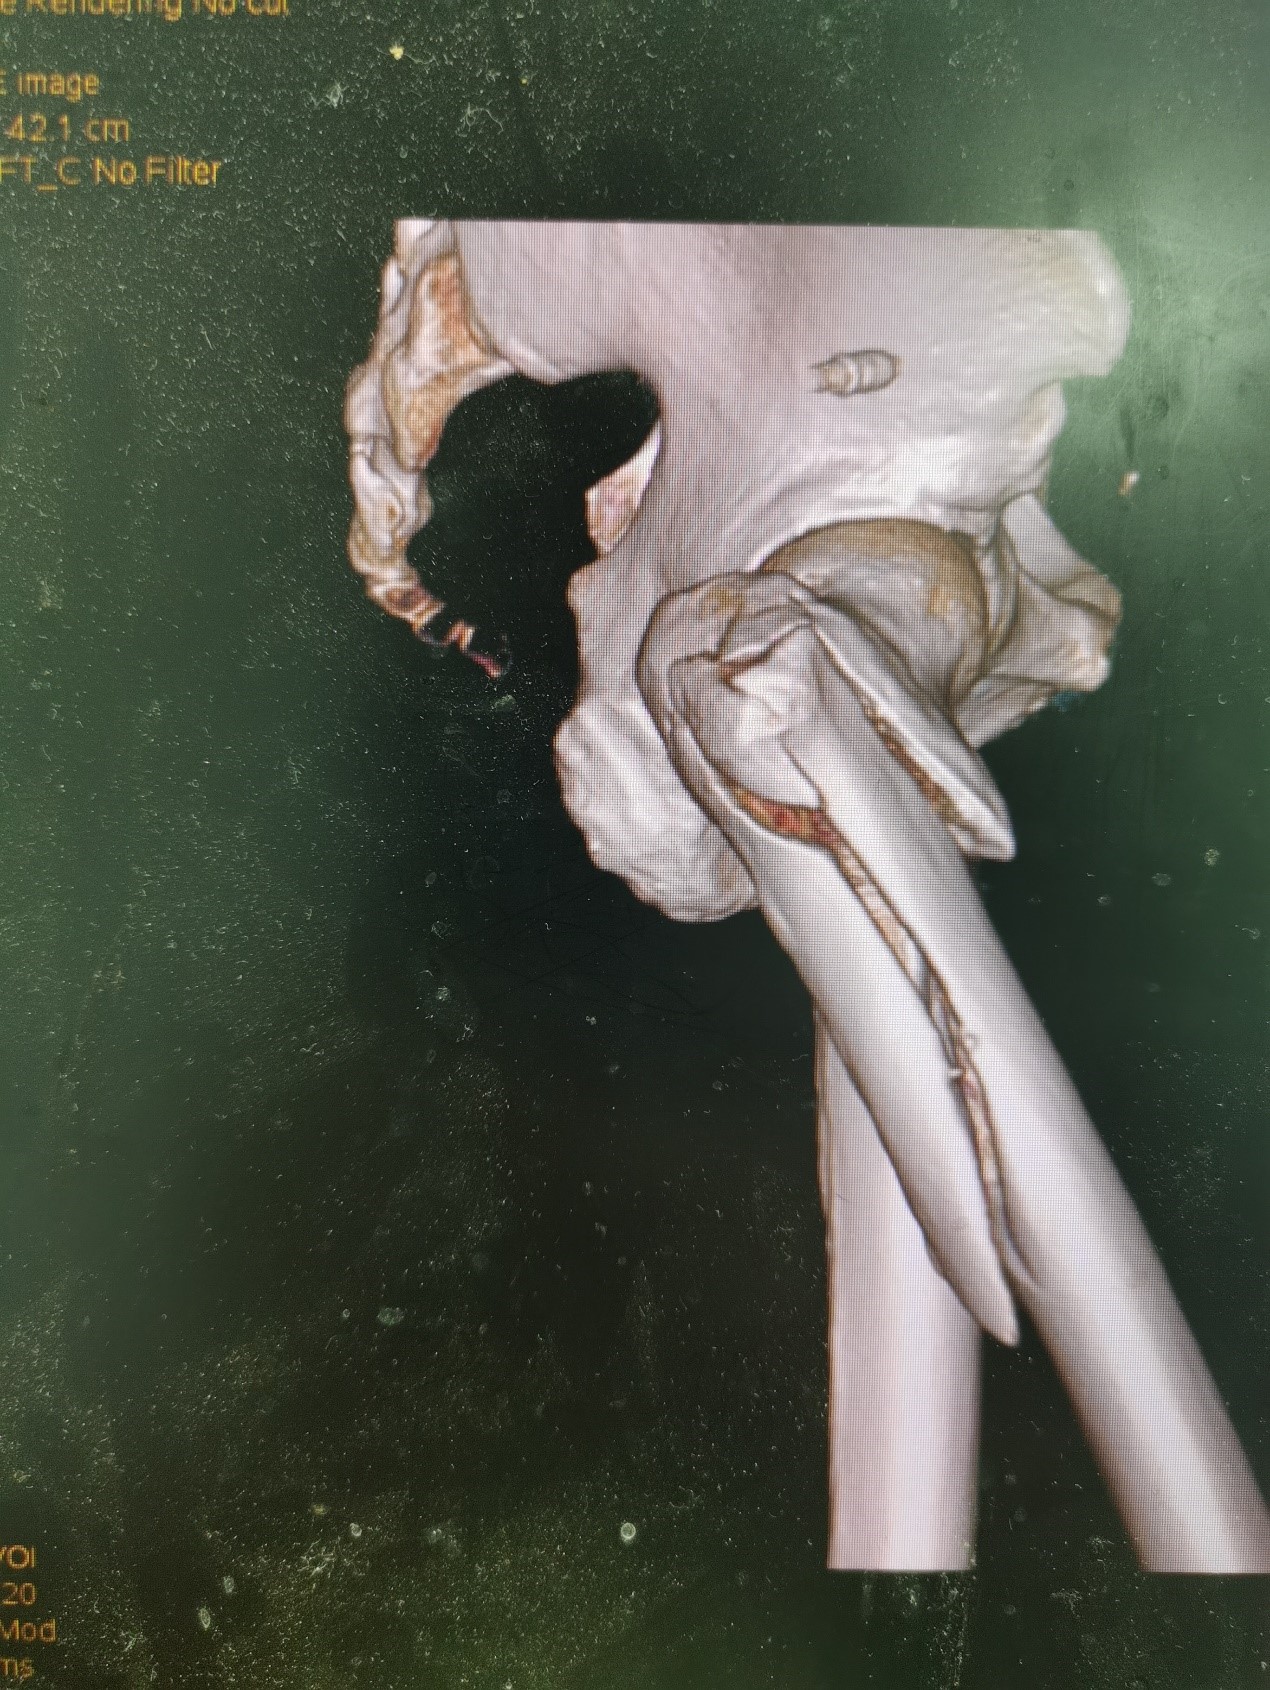

1.摔伤后需评估假体是否松动;

2.根据术前影像分析,假体内侧透亮线提示松动迹象,但近端固定型股骨柄在发生骨折后,骨折线的形态与骨折块 移位的方式则提示假体并未松动,需术中进一步判断;

3.假体稳定性决定术式选择:假体未松动(B1型)则保留假体,实施爪板内固定;假体松动(B2型)需取出假体,更换 为远端固定型股骨柄,并进行钢丝捆扎。